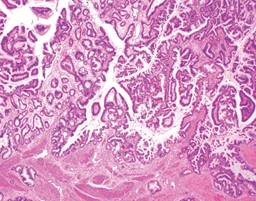

Masculino de 64 años, quien inicia su padecimiento con ictericia, negando otra sintomatología, llama la atención que se manifesta durante al menos tres días previos a su llegada a urgencias, su exploración física sin alteraciones, los laboratorios revelan una bilirrubina total de 25 mg/dl, bilirrubina directa de 22 mg/dl, fosfatasa alcalina 235 UI/l, gamma-glutamil transferasa 157 UI/l, creatinina 2.5 mg/dl, el resto de los laboratorios normales, se le realiza un ultrasonido de abdomen que reporta vesícula biliar mal definida, y dilatación de la vía biliar de 19 mm (Figura 1), se observa lito en colédoco de alrededor de 12 mm. Se integra el diagnóstico de coledocolitiasis, no obstante, se solicitan marcadores tumorales, con reporte de CA 19-9 de +8,000 UI; se solicita colangiorresonancia, la cual evidencia dilatación de vía biliar (vb) de 20 mm, lito de 16 mm a nivel del ámpula, no se reporta morfología de la vesícula biliar (VB), paciente candidato a colangiopancreatografía retrógrada endoscópica (CPRE) según el servicio de Gastroenterología. Se le realiza CPRE sin poder extraer lito, se programa para colecistectomía con exploración de vía biliar, el transoperatorio revela biliperitoneo, lisis de VB, fístula colecistocoledociana (Figura 2), litio único de 15 mm, se coloca sonda T, no se cuenta con servicio de cirugía hepatopancreatobiliar, por lo que no se realiza reparación definitiva, colangiografía transoperatoria revela paso de material de contraste a duodeno, sin fugas aparentes por orificio fistuloso (Figura 3), evolución posoperatoria favorable, el drenaje por sonda T en promedio 500 ml por día con disminución progresiva, con mejoría de hiperazoemia, con flujo urinario mayor a 0.5 ml/kg/h, colangiografía posoperatoria sin fugas, paso de medio de contraste a duodeno, reporte de patología revela adenocarcinoma de vesícula moderadamente diferenciado con infiltración a muscular (Figura 4). El paciente rechaza tratamiento médico y decide egreso voluntario, comprende y acepta los riesgos, no contamos con seguimiento a largo plazo.

Por otro lado, el CAVB es el cáncer más frecuente de la vía biliar, 80% con respecto al colangiocarcinoma, se encuentra de manera más común en fundus (60%), cuerpo (30%) y cuello (10%), el tipo histológico más frecuente es el adenocarcinoma, se considera invasor al sobrepasar la muscularis propia, es decir, los estadios T1a (Figura 4); es frecuente encontrar casos con perforación del peritoneo visceral e invasión a órganos adyacentes, sin embargo, el diagnóstico intraoperatorio y tratamiento radical sólo se realiza en menos de 1% de los casos.8-10